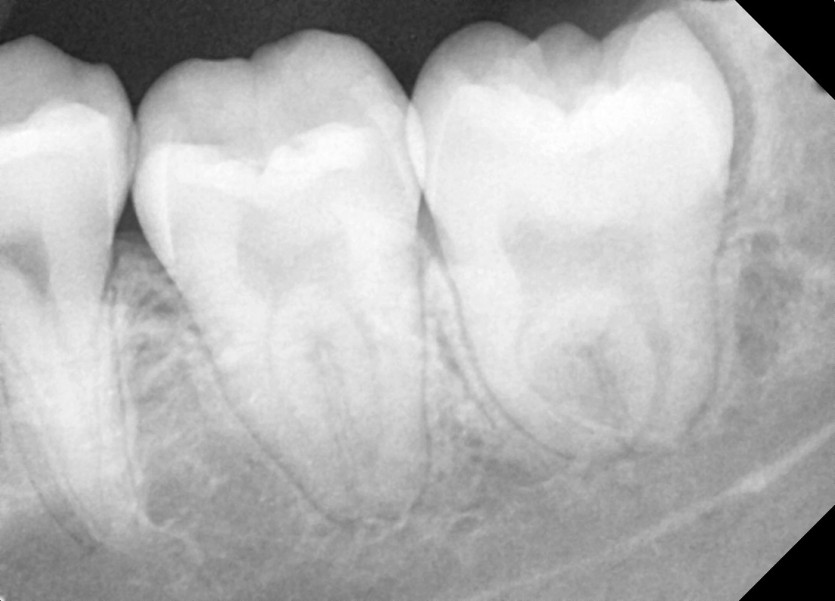

#38 사랑니 발치

구강외과 전문의가 당일 발치했습니다.